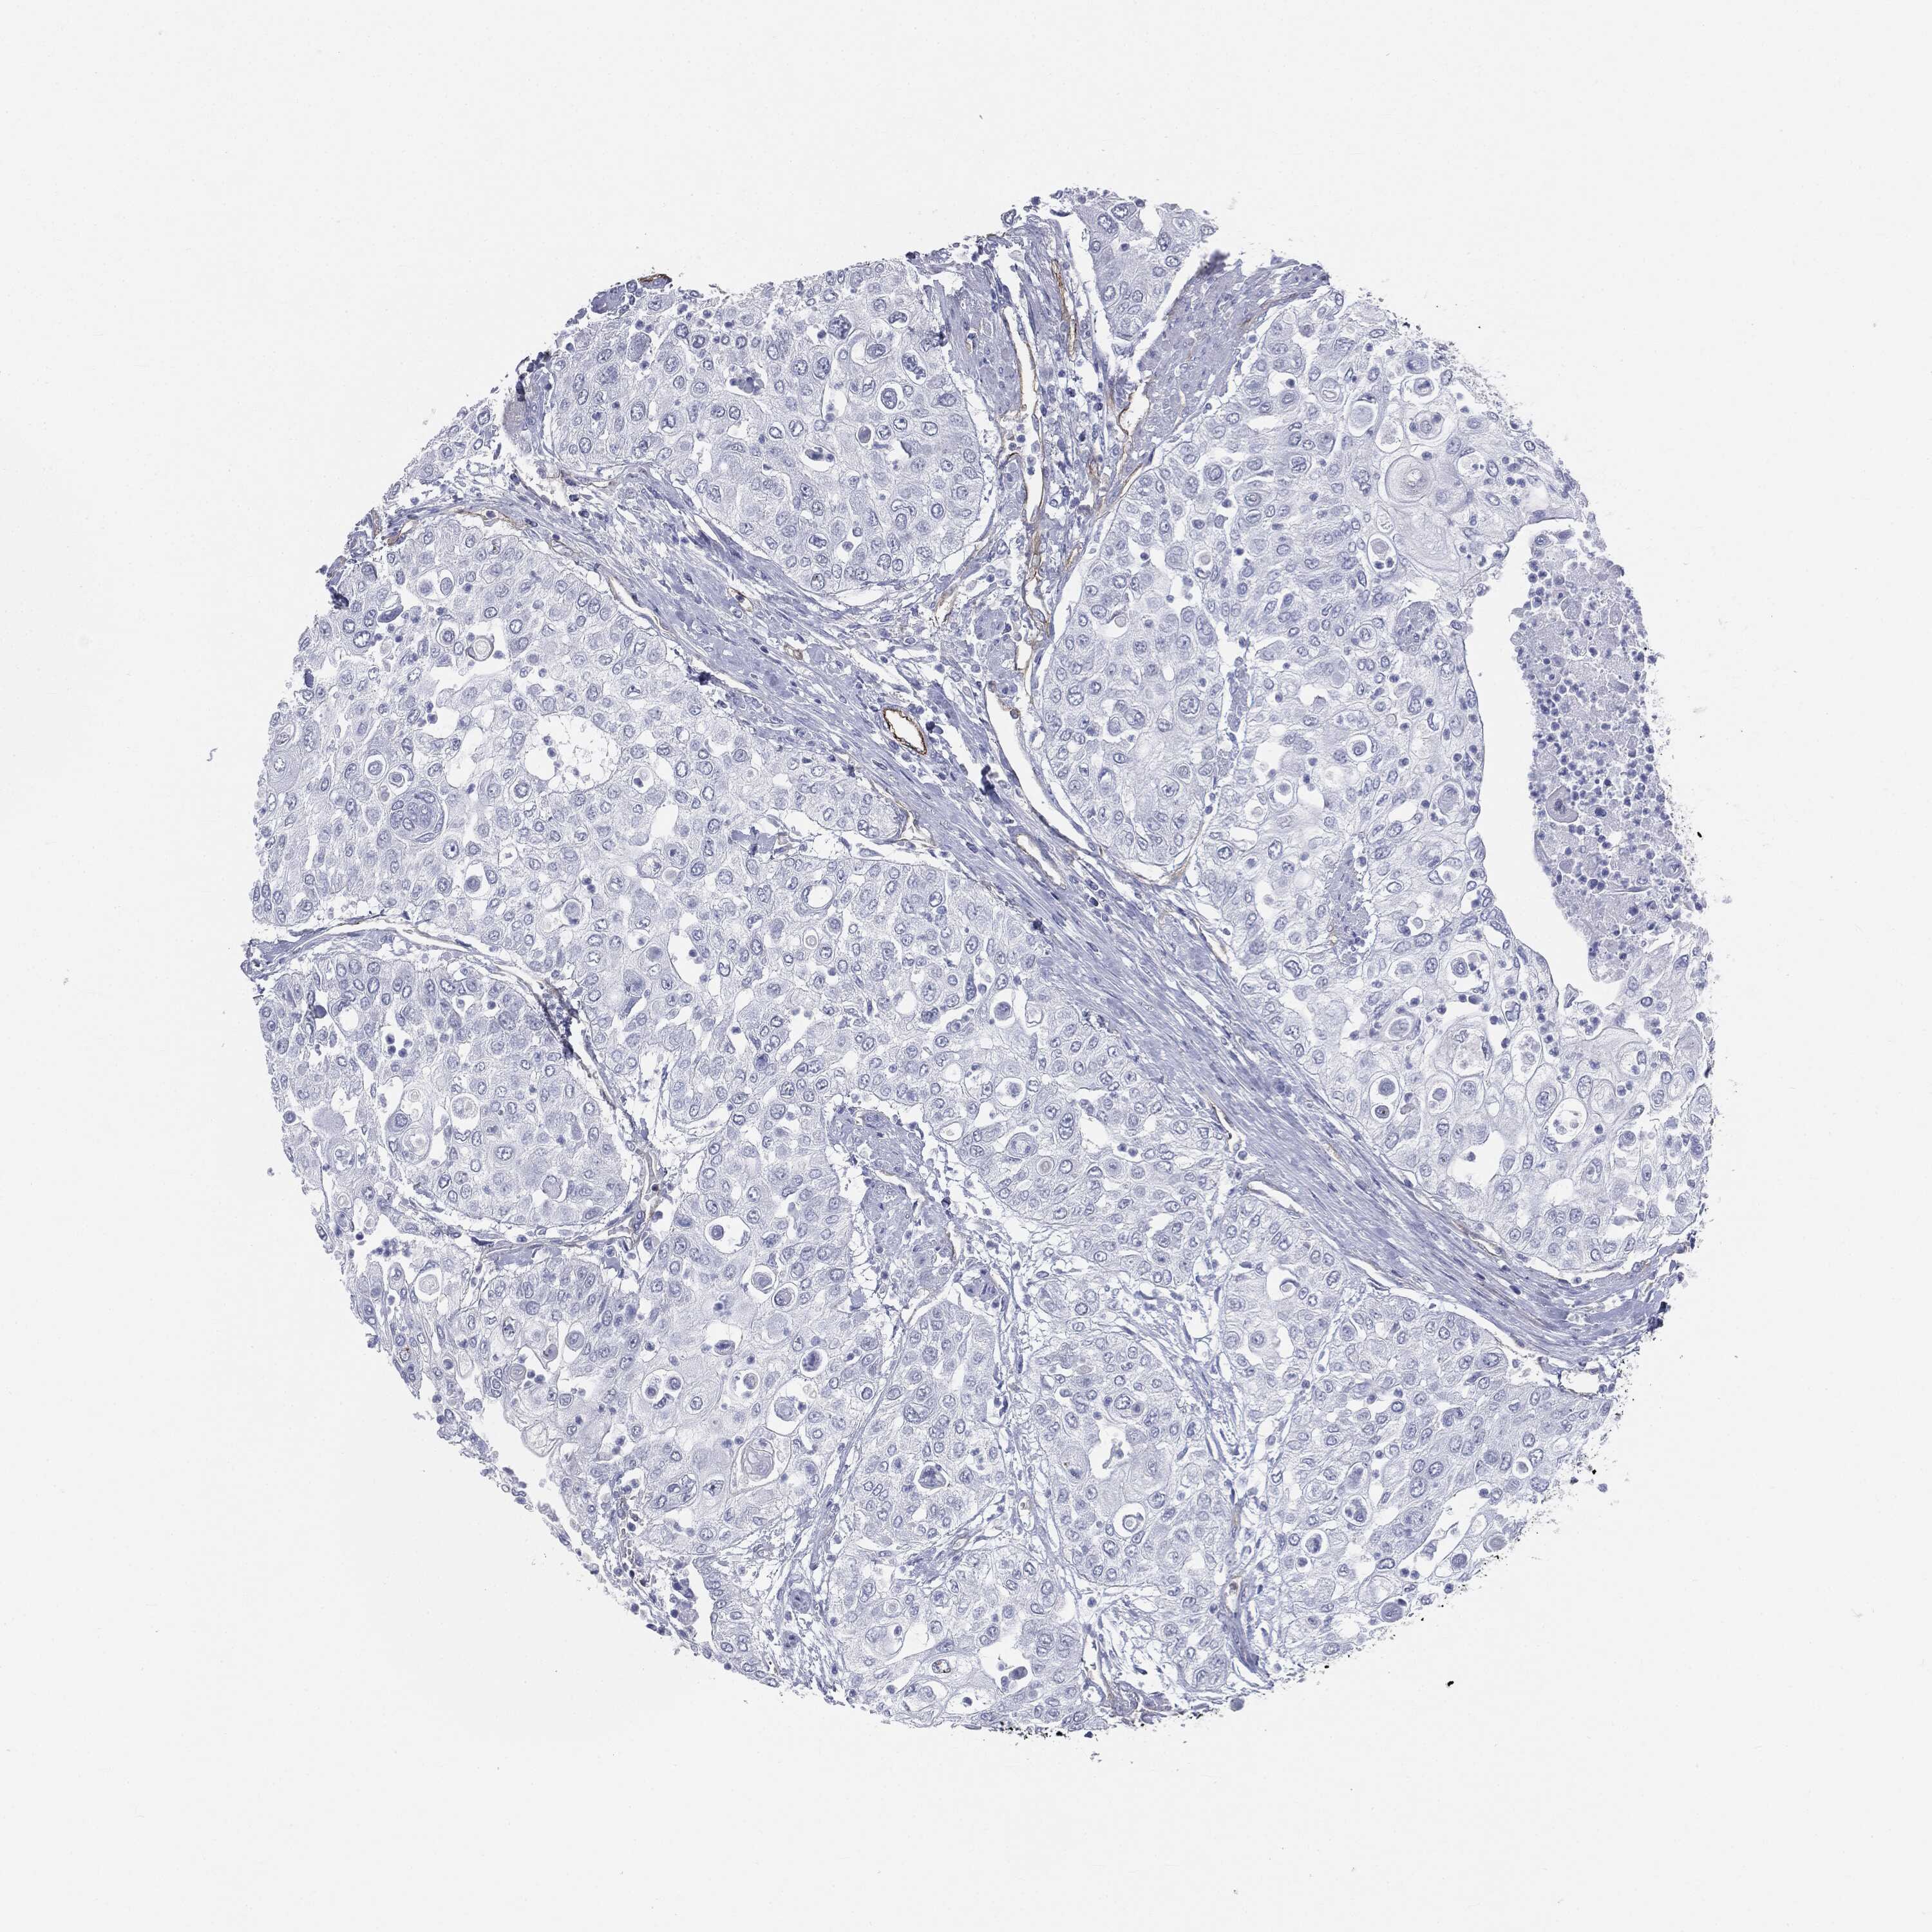

UROTHELIAL CANCER - Protein expressioni

A mouse-over function shows sample information and annotation data. Click on an image to view it in a full screen mode. Samples can be filtered based on level of antibody staining by selecting one or several of the following categories: high, medium, low and not detected. The assay and annotation is described here.

Note that samples used for immunohistochemistry by the Human Protein Atlas do not correspond to samples in the TCGA dataset.

Antibody stainingi

Antibody staining in the annotated cell types in the current human tissue is reported as not detected, low, medium, or high, based on conventional immunohistochemistry profiling in selected tissues. This score is based on the combination of the staining intensity and fraction of stained cells.

Each image is clickable and will lead to virtual microscopy that enables deeper exploration of all samples and also displays staining intensity scores, fraction scores and subcellular localization as well as patient and tissue information for each sample.

Urothelial carcinoma, High grade

Urothelial carcinoma, NOS

Urothelial carcinoma, Low grade

Adenocarcinoma, NOS